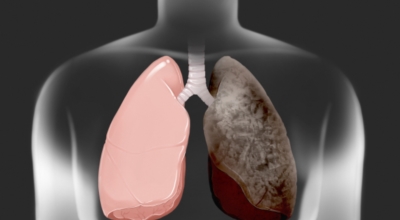

폐암의 공통 위험요소로 손꼽히는 이유가 되는 것으로 흡연이 있어요. 흡연자는 비흡연자에 대조해 십몇 배는 더 폐암 발병확률이 높다고 하며 어느정도 기간 동안 흡연했는지에 따라 폐암 발생확률은 더욱 더 높아집니다. 흡연자라고 해도 금연을 하게 되면 폐암 발병확률이 빠르게 낮아진다고 하니 폐암이 걱정되신다면 가장 먼저 금연은 필수입니다.

간접흡연 외에도 공사장과 같은 곳에서 미세먼지나 석면, 비소, 라돈, 카드뮴 등 육체에 나쁜 성분에 노출되는 환경적 요인으로 폐암이 발병할 수 있으며 유전적 요인으로도 폐암이 발병할 수 있다고 하죠. 가족 중 폐암을 앓았던 분들이 있다면 그렇지 않은 분들에 대조해 2배 가량 더 폐암에 걸릴 확률이 높다고 하는데요 이렇듯 폐암은 나도 모르는 새에 발병할 수 있기 때문에 자신의 체력 상태를 자주 체크하여 폐암을 초기에 발견하는 것이 현명합니다.